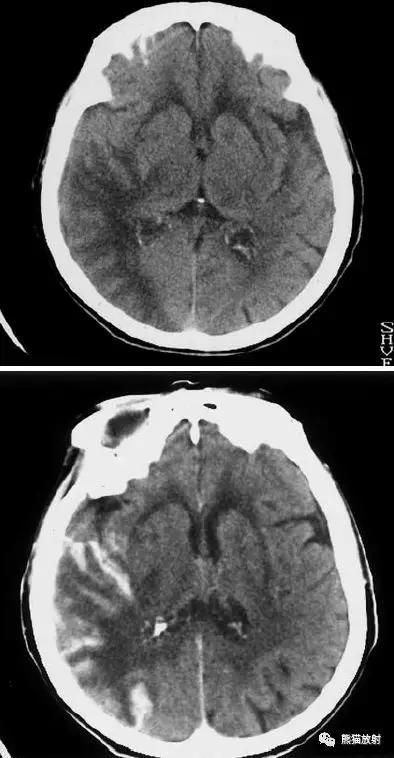

大脑中动脉区梗死:部分梗死,仅累及左侧浅表区域。

左侧大脑中动脉区完全梗死,对邻近的侧脑室产生占位效应;右侧可见其他较小的缺血性低密度区。